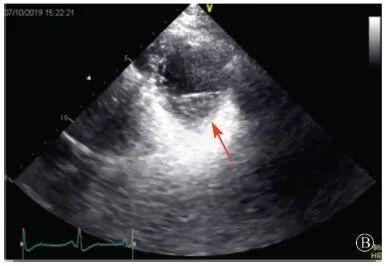

患者入院后無特殊不適,心率70次/min,血壓110/60 mmHg,心功能Ⅱ級。查血常規(guī):血紅蛋白139 g/L,白細胞7.39×109/L,血小板221×109/L。尿常規(guī)、便常規(guī)+潛血均正常。生化:丙氨酸氨基轉(zhuǎn)移酶38 U/L,白蛋白47 g/L,鉀3.9 mmol/L,肌酐(酶法)65 μmol/L,總膽固醇3.52 mmol/L,低密度脂蛋白膽固醇2.08 mmol/L。CK:1256→487 U/L,CK-MB 9.7→3.8 μg/L,cTnI 85.90→68.50 pg/ml。N末端B型利鈉肽原70 pg/ml。CK同工酶電泳:肌酸激酶MM質(zhì)量100.0%(此時CK-MB已正常)。血沉1 mm/第1小時,高敏C反應(yīng)蛋白1.61 mg/L;補體:C3 0.876 g/L,C4 0.174 g/L。免疫球蛋白:IgG 9.52 g/L,IgA 1.73 g/L,IgM 0.62 g/L。血清蛋白電泳未見M蛋白。糖化血紅蛋白5.1%。乳酸(運動前)1.1 mmol/L,乳酸(運動中)6.6 mmol/L,乳酸(運動后)7.8 mmol/L。肌炎抗體譜:抗PM-SCL75(+),余均(-)。心電圖:aVL、V5、V6導聯(lián)T波倒置(圖2)。冠狀動脈CT未見明顯異常。超聲心動圖:左室舒張末內(nèi)徑55 mm,左室收縮功能減低,心尖部、左室壁普遍運動減低,以左室下后壁為著,左室下后壁肌小梁明顯增多可見隱窩,疏松層與致密層之比為1.7;左室射血分數(shù)(雙平面)45%;右冠狀動脈開口6.5 mm,開口處未見明確瘤樣擴張(圖3)。

B:胸骨旁左室短軸切面心尖水平,可見心肌肌小梁增多,其內(nèi)可見隱窩(箭頭所示)

圖3 患者入院后超聲心動圖

入院后經(jīng)過初步篩查發(fā)現(xiàn),患者血尿便常規(guī)、生化指標均大致正常,無炎性指標升高,無特異性免疫指標異常,冠狀動脈無受累??紤]免疫病活動或急性病毒感染可能性較小,臨床表現(xiàn)偏向于慢性心肌病變合并長期CK升高。患者血清蛋白電泳、乳酸運動試驗的陰性不符合輕鏈型淀粉樣變、線粒體肌病等少見病的表現(xiàn)。患者超聲心動圖可見左室下后壁肌小梁明顯增多,疏松層增厚,但尚未達到診斷左室心肌致密化不全(left ventricular noncompaction,LVNC)的標準,且LVNC并不能解釋本患者CK明顯升高的情況。心肌致密化不全的發(fā)病機制目前不有效清楚,很多心肌疾病可出現(xiàn)心肌肌小梁的增多,類似心肌致密化不全的形態(tài)改變。行乳酸運動試驗的過程中,患者表現(xiàn)出對持續(xù)的蹲起運動的無法耐受,雖然此前四肢肌力正常,但雙側(cè)腓腸肌肥大、大腿近端肌力耐力較差,提示存在慢性肌肉病變。應(yīng)積極完善雙大腿磁共振成像、肌肉活檢及肌營養(yǎng)不良相關(guān)基因檢測。